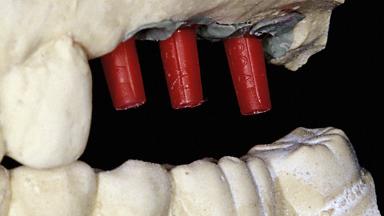

This 65-year-old female patient presented for implantbased restoration of the maxillary posterior region (25–27). Although this patient was free of medical compromise, her treatment was associated with several modifying factors. She had been a patient of record in the practice for more than twenty years. Her initial treatment included extraction of the failing maxillary left first molar, and restoration with a fixed dental prosthesis (25–27) and crown (24). At the time of initial restoration, implants were not considered appropriate options for the replacement of single posterior teeth.